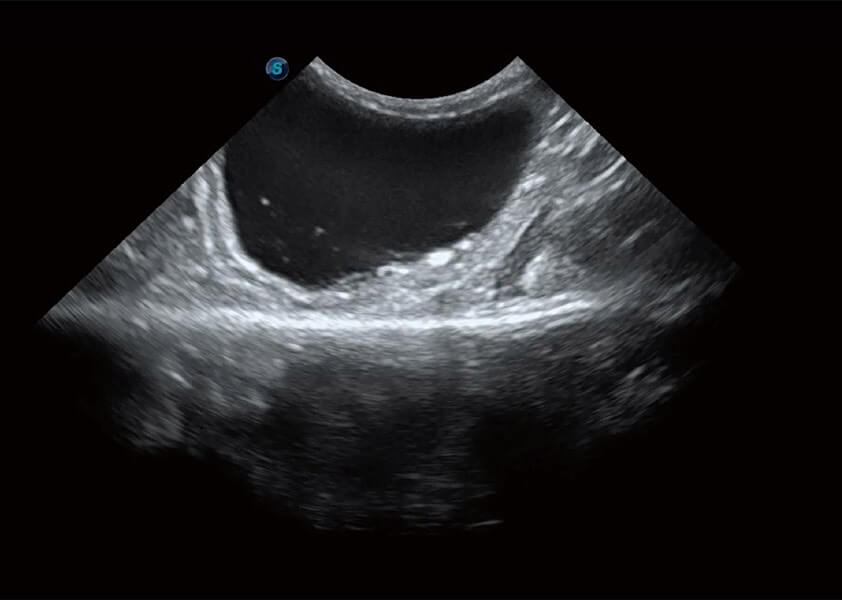

ProPet 60 作為一款高端臺式動物超聲設備,為動物醫(yī)生的日常診斷提供了一系列貼合動物臨床需求、解決臨床實際問題的高級成像功能。憑借全系列高清探頭,滿足醫(yī)生對腹部、心臟、生殖、淺表、肌骨等成像的所有需求,切實幫助您提升檢查效率,提高診斷信心。